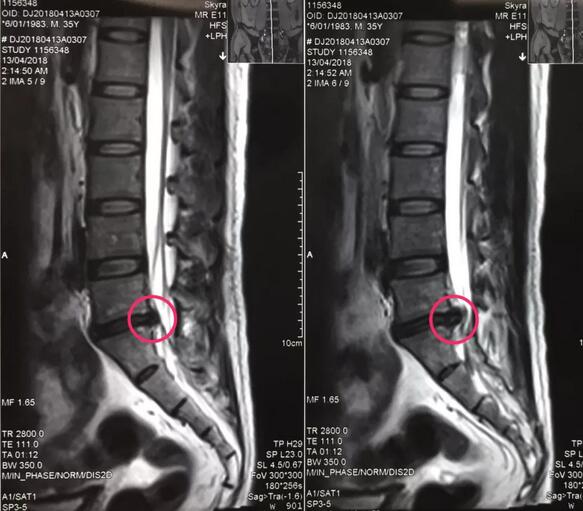

八零后李先生来自山西长治,是家里的顶梁柱,半年前开始出现腰痛不适,工作繁忙没有时间看病,后来突然加重并出现左下肢放射样抽痛,走路都走不了,在当地多家医院检查确诊为腰椎间盘突出症,治疗方案都是开刀手术,打钉固定,小李拒绝开放手术,回家卧床四个多月,仍然不能下地走路,亲朋友好友四处寻医问药,终于从病友群里打听到,91论坛 可以微创手术,效果很好,就专程前来。骨一科专家团队给李先生进行了详细的查体和认真的读片,告诉李先生诊断确实是腰椎间盘突出症,适合孔镜微创,不用开放手术,不用打钉固定,李先生欣然接受。7月27日,骨一科微创团队为李先生实施了经皮椎间孔镜下髓核摘除术,手术一小时,术后下肢抽痛症状完全解除,终于可以下地走路了,李先生和家人对手术效果非常满意。